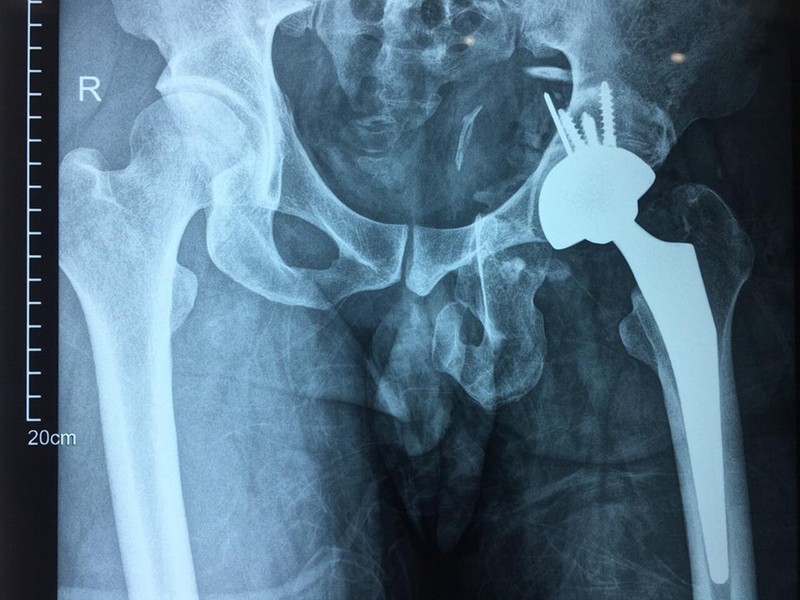

Phim chụp X-quang của bệnh nhân sau phẫu thuật thay khớp háng. Ảnh: Bệnh viện Hữu nghị Việt Đức

Sau vụ tai nạn, bệnh nhân xuất hiện các vết thương ở tầng sinh môn, hậu môn nhân tạo, vết thương dập nát vùng mông,… điều kiện vết thương chưa cho phép để mổ thay khớp háng. Do tổn thương nặng, ổ cối bị biến dạng, chỏm bị trật lâu ngày, anh T. đã bị tiêu chỏm xương đùi, mất chức năng vận động của khớp háng (gấp, duỗi, dạng, xoay, khép, đi, đứng). Không chỉ vậy, anh T. còn phải chịu nhiều đau đớn do tình trạng ngắn chi gây ra (chân trái ngắn hơn chân phải khoảng 3-4cm). Điều này khiến anh T. đi lại khó khăn, hạn chế vận động, ảnh hưởng đến khả năng lao động và gây khó khăn trong cuộc sống sinh hoạt hàng ngày.

Thực tế, với người bệnh trẻ tuổi, đến sớm, không kèm theo những vết thương phần mềm khác gây ra nguy cơ nhiễm trùng thì các bác sĩ sẽ chỉ định đặt lại khớp háng kết hợp xương khung chậu. Tuy nhiên, đây là trường hợp khó vì người bệnh đến bệnh viện muộn, sau chấn thương 1,5 năm, xương chậu bị vỡ nát, trật khớp háng lâu ngày, chỏm xương đùi bị tiêu, đã hỏng sụn khớp. Nếu có mổ đặt lại khớp háng kết hợp xương khung chậu cũng không mang lại hiệu quả như mong muốn nên các bác sĩ đã quyết định phẫu thuật thay lại khớp háng cho người bệnh. Khi tổn thương khớp háng không thể hồi phục thì việc thay toàn bộ khớp háng là lựa chọn tốt nhất cho người bệnh.

Để “sửa chữa” di chứng đa chấn thương cho bệnh nhân, PGS. TS. Nguyễn Mạnh Khánh và ê kíp đã tiến hành ghép xương và tạo hình lại ổ cối để chuẩn bị cho việc đặt lại ổ khớp mới.

Đáng chú ý, các bác sĩ đã tiến hành thay khớp háng thế hệ mới - khớp háng không xi măng và 2 chuyển động. Đây là loại khớp đặc biệt có giá trị với bệnh nhân trẻ. Khớp cố định vững chắc giúp biên độ vận động khớp háng rộng, hạn chế mức tối đa nguy cơ bị trật khớp háng, độ mài mòn của khớp ít. Từ đó, tuổi thọ khớp được kéo dài, tối thiểu 30-40 năm. Sau phẫu thuật, người bệnh có thể vận động sớm, phục hồi nhanh.